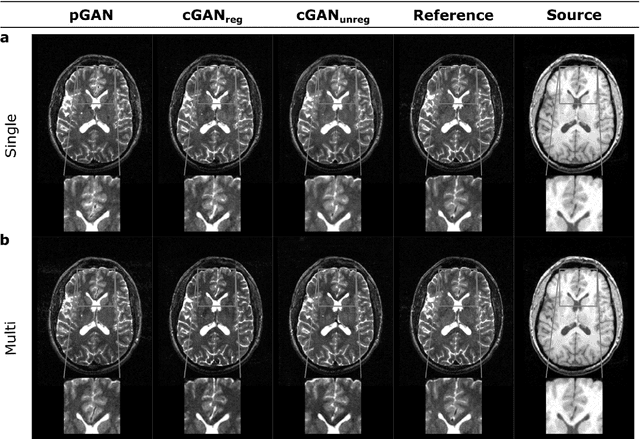

Abstract:Acquiring images of the same anatomy with multiple different contrasts increases the diversity of diagnostic information available in an MR exam. Yet, scan time limitations may prohibit acquisition of certain contrasts, and images for some contrast may be corrupted by noise and artifacts. In such cases, the ability to synthesize unacquired or corrupted contrasts from remaining contrasts can improve diagnostic utility. For multi-contrast synthesis, current methods learn a nonlinear intensity transformation between the source and target images, either via nonlinear regression or deterministic neural networks. These methods can in turn suffer from loss of high-spatial-frequency information in synthesized images. Here we propose a new approach for multi-contrast MRI synthesis based on conditional generative adversarial networks. The proposed approach preserves high-frequency details via an adversarial loss; and it offers enhanced synthesis performance via a pixel-wise loss for registered multi-contrast images and a cycle-consistency loss for unregistered images. Information from neighboring cross-sections are utilized to further improved synthesis quality. Demonstrations on T1- and T2-weighted images from healthy subjects and patients clearly indicate the superior performance of the proposed approach compared to previous state-of-the-art methods. Our synthesis approach can help improve quality and versatility of multi-contrast MRI exams without the need for prolonged examinations.